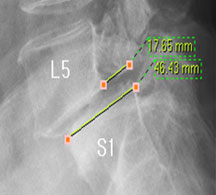

모커리한방병원 함○○ (55, 여) 척추전방전위증 2단계 실제치료사례 이미지

함○○ (55, 여) 척추전방전위증 2단계 입원치료기간 : 30일

입원시 퇴원시

허리 통증지수(NRS) 7 1

엉덩이 통증지수(NRS) 7 1

통증없이 걷는거리(m) 20m

(보조기 착용하고 하루 1회)

100m

(보조기 없이 하루 수회 각각)